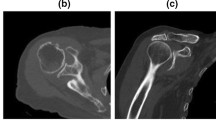

Radiological evaluation of rotator cuff tendon damage and glenohumeral arthritis was performed based on the available conventional X-rays, CT and MRI scans (Figs. 1a–d, 2a–c). Table 1 shows the results of radiological assessment of orthopaedic and trauma shoulders (4-part or Neer Type VI dislocated proximal humerus fractures).

According to the Walch classification, grade ‘D’ in the case of sample B2 indicates a very severe arthritis with anterior humeral head subluxation and level ‘A1’ in the case of sample A3 means a well-centred humeral head with only minor erosions. Based on MRI scans, Outerbridge ‘grade 2’ of sample B1 means blister-like swelling/fraying of articular cartilage extending to surface, a moderately damaged cartilage. The Hamada classification indicates the progression of rotator cuff tear arthropathies (from 1 to 5). Of the trauma samples, A3 was graded as ‘4b’ and orthopaedic samples B1 and B2 were graded as ‘4A’ and ‘5’, respectively, demonstrating a worse prognosis of arthropathy for the orthopaedic patients.